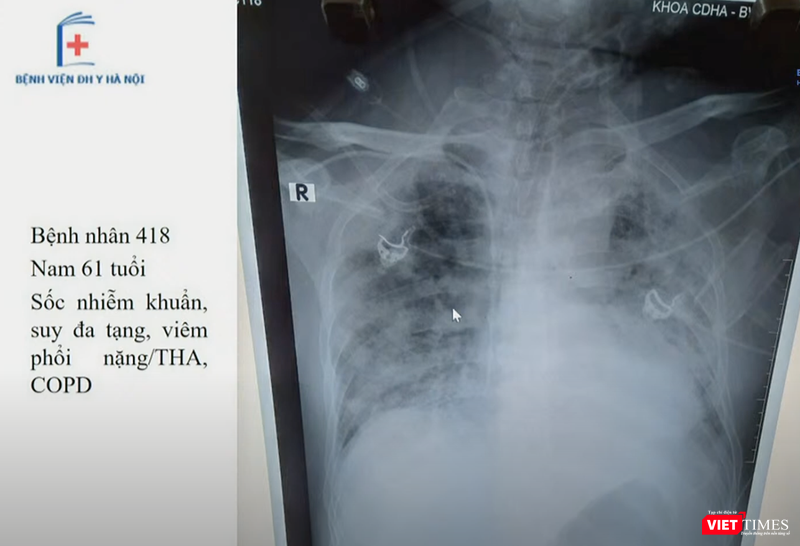

Tại buổi hội chẩn, TS. Lưu đã phân tích hình ảnh X-quang phổi củav một số bệnh nhân COVID-19 đã tử vong, để cho thấy các bệnh nhân đều có tổn thương phổi điển hình.

![]() |

|

Hình ảnh X-quang phổi của 1 bệnh nhân mắc COVID-19 (Ảnh: Bệnh viện Đại học Y Hà Nội)

Chẩn đoán viêm phổi do COVID-19 qua hình ảnh X-quang

Để chẩn đoán và điều trị viêm phổi do COVID-19 chính xác, việc nắm rõ các triệu chứng qua hình ảnh X-quang và cắt lớp vi tính của viêm phổi virus nói chung và viêm phổi do COVID-19 nói riêng, là vô cùng quan trọng.

Thông tin về hình ảnh X-quang, chụp cắt lớp vi tính của bệnh nhân mắc COVID-19, TS. Đoàn Tiến Lưu – Phó trưởng Khoa Chẩn đoán hình ảnh, Bệnh viện Đại học Y Hà Nội – cho biết: Việc chụp X-quang có độ nhạy không cao với tổn thương ở phổi (tổn thương tổ chức kẽ, kính mờ) của bệnh nhân COVID-19, còn chụp cắt lớp vi tính có độ nhạy cao, phát hiện được đặc điểm tính chất tổn thương phổi của người bệnh.

TS. Lưu nhấn mạnh: Hình ảnh X-quang, cắt lớp vi tính đóng vai trò quan trọng trong việc đánh giá mức độ tổn thương phổi của người bệnh, đồng thời, theo dõi tiến triển của phổi. Dù người bệnh có kết quả xét nghiệm Realtime-PCR âm tính với virus SARS-CoV-2 , nhưng nếu hình ảnh X-quang phổi có dấu hiệu nghi ngờ thì vẫn phải xét nghiệm lại để khẳng định.

Qua các ca bệnh mắc COVID-19, các bác sĩ phát hiện hình ảnh X-quang phổi có tổn thương chủ yếu ở ngoại vi (58%) và đáy phổi (59%), phần lớn là ở 2 bên phổi (69%).